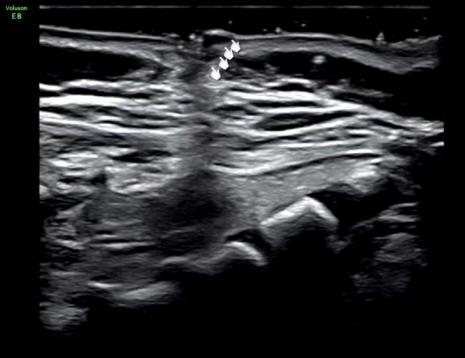

出生后,超声医生曝光了我在宝宝骶尾部的「躲藏」之路

看到这里,其实也不要过于担忧,悄悄告诉你,我也有害怕的时候。我害怕医院的影像学医生,因为他暴露了我的「秘密」通道(超声检查可以准确地显示并评估皮毛窦的形态、部位和走行方向、是否与椎管内相通、圆锥位置是否低、圆锥末端有无异常回声出现外,还可行 MRI 检查,尽可能发现合并的其他异常),更害怕外科医生,因为他一言不合就「开打」,毕竟我最大的威胁是手术。

如果产前超声检查能准确地显示并评估皮毛窦的形态、部位和走行方向、是否与椎管内相通、圆锥位置是否低、圆锥末端有无异常回声,能为宝宝出生后的治疗和随访观察提供坚实有利的依据。